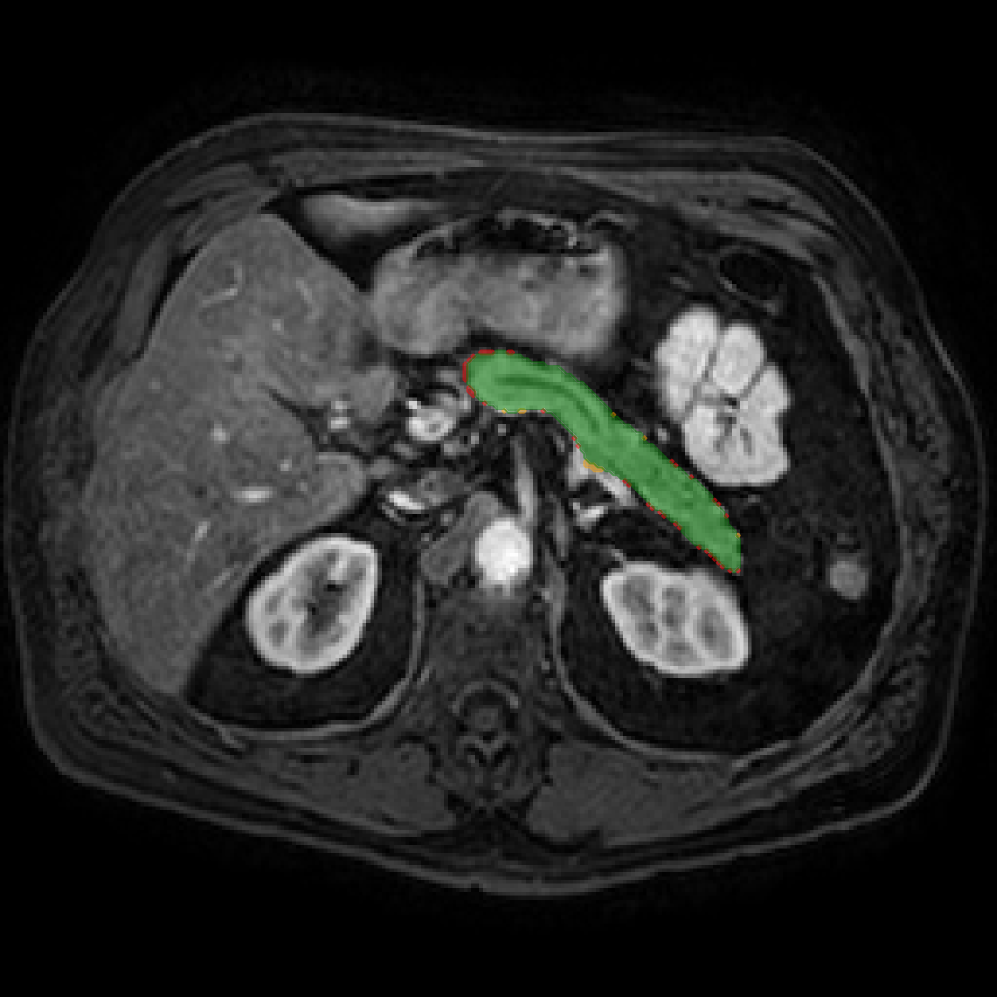

Accurate pancreas segmentation is a critical prerequisite for precise cyst analysis and classification. Recently, we developed PanSegNet [zhang2025large], a novel segmentation architecture incorporating linear self-attention layers [zhang2022dynamic] within the nnUNet framework [isensee2021nnu] to enhance global information modeling capabilities while maintaining computational efficiency (Fig. 1). PanSegNet demonstrated exceptional segmentation performance across both T1W and T2W modalities, achieving mean dice scores of 86.817.30% and 89.626.38%, respectively (Table 1, Fig. 2b-c). This performance significantly exceeded that of Swin-UNETR [hatamizadeh2021swin], one of the most used state-of-the-art transformer-based medical segmentation models, which achieved dice scores of 79.091.40% and 76.290.66% for T1W and T2W, respectively (). In this study, we integrated PanSegNet into our Cyst-X engine along with a classifier for risk prediction. In Section 2.2, we show that the choice of segmentation model affects the classification results. The performance advantage of PanSegNet was consistent across all seven medical centers, demonstrating robust generalization despite variations in imaging protocols and equipment (Table 1). This cross-institutional reliability is particularly important for clinical applications, where model performance must remain consistent regardless of imaging site or acquisition parameters.

2.2.1 Importance of accurate pancreas segmentation in classification

To assess the importance of accurate pancreas segmentation in classification, we evaluated how different ROI sources affect DenseNet-121’s performance. Specifically, we compared classification results using ROIs generated by PanSegNet and Swin-UNETR, both under centralized learning, against a baseline using radiologist-defined ROIs. As shown in Table 2, using PanSegNet’s masks resulted in only a modest performance decline, reflecting its strong segmentation quality. In contrast, Swin-UNETR led to a more substantial drop, demonstrating that inferior segmentation can directly compromise classification. For 3-class classification, the mean AUC dropped from 75.59% (radiologist ROI) to 72.26% with PanSegNet, and further to 66.95% with Swin-UNETR on T1-weighted images. On T2-weighted scans, the AUC declined from 81.09% to 74.18% (PanSegNet) and to 69.63% (Swin-UNETR). A similar trend was observed in 2-class classification: on T1W, AUC dropped from 78.13% to 74.84% (PanSegNet) and 70.20% (Swin-UNETR); on T2W, from 82.37% to 77.01% and 68.92%, respectively. These results emphasize that accurate segmentation—particularly via PanSegNet—is not only essential for volume estimation but also critical to preserving downstream classification performance in the Cyst-X pipeline.